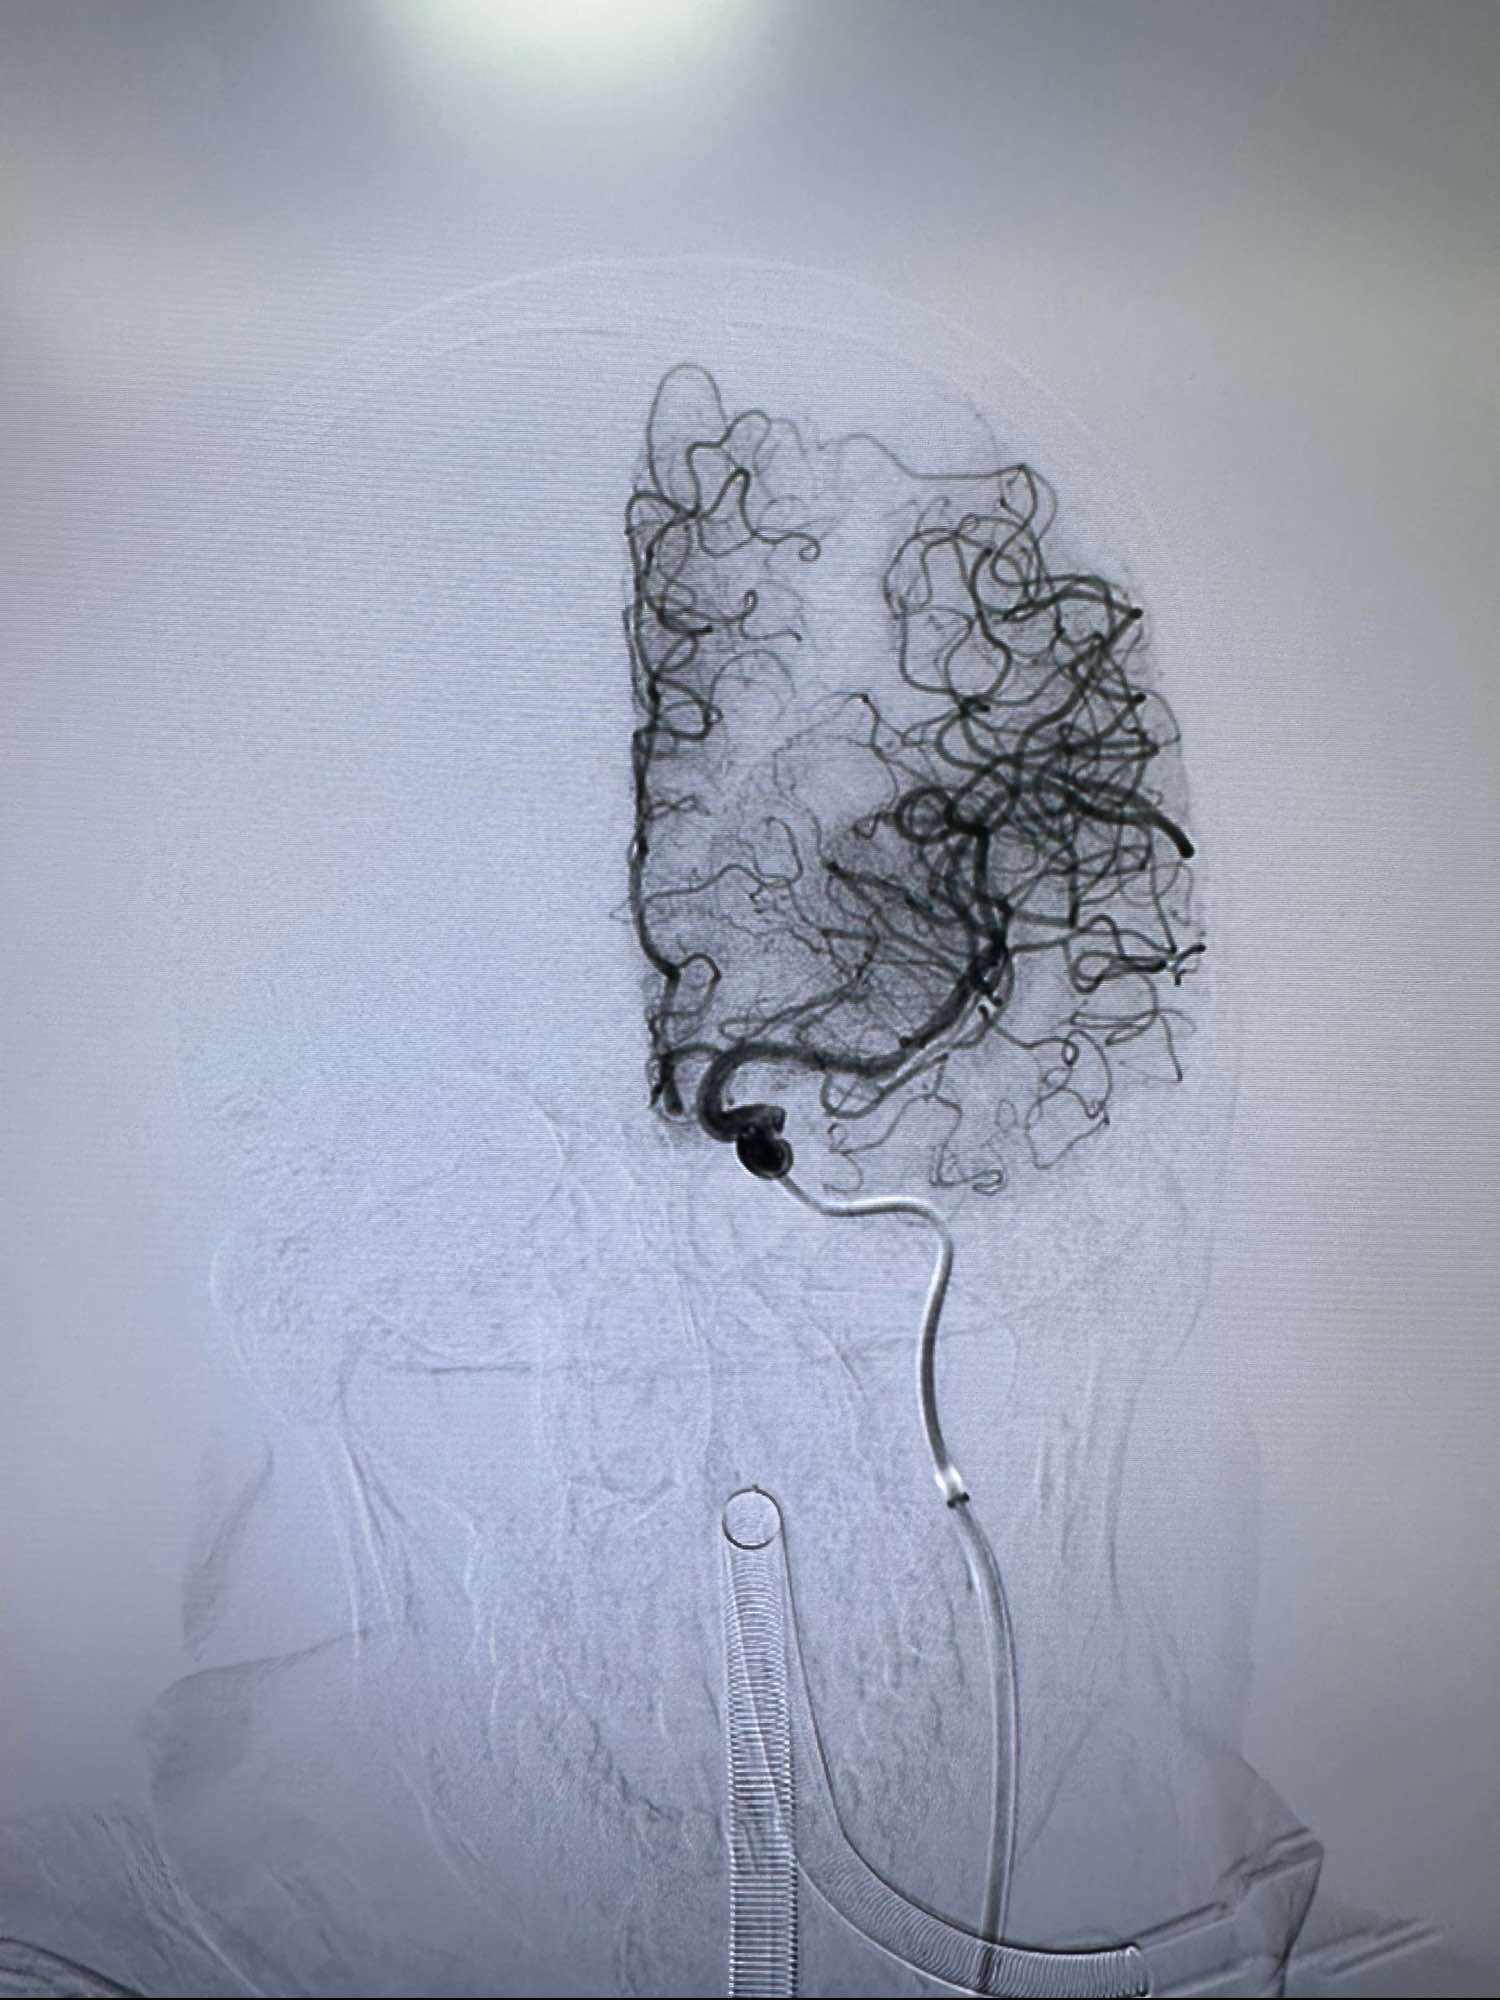

最后正位造影

侧位

侧位的动脉晚期